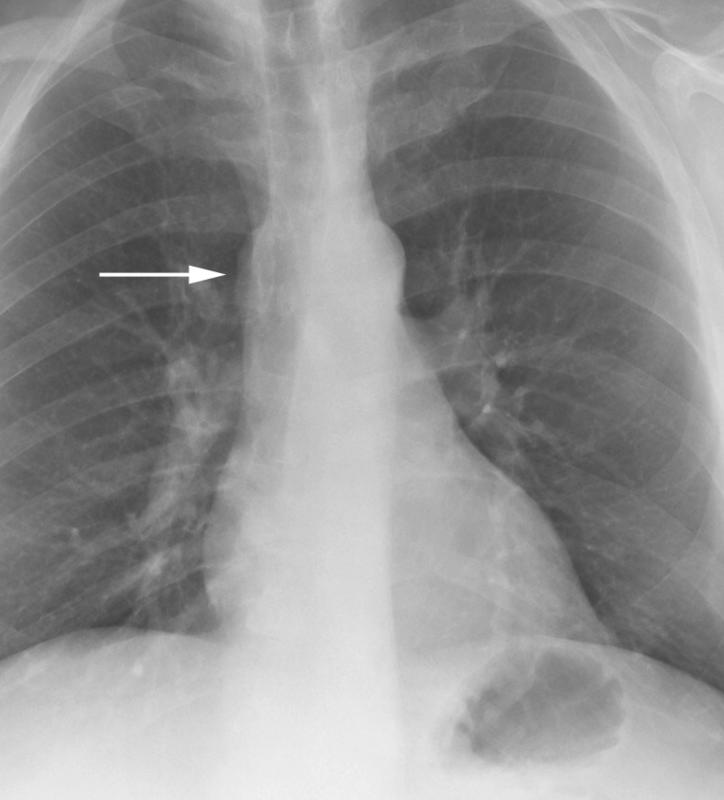

Gallery Congenital Azygous continuation

Azygous continuation